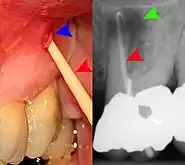

Apical periodontitis is acute or chronic inflammation around the apex of a tooth caused by an immune response to bacteria within an infected pulp.[23] It does not occur because of pulp necrosis, meaning that a tooth that tests as if it's alive (vital) may cause apical periodontitis, and a pulp which has become non-vital due to a sterile, non-infectious processes (such as trauma) may not cause any apical periodontitis.[12]: 225 Bacterial cytotoxins reach the region around the roots of the tooth via the apical foramina and lateral canals, causing vasodilation, sensitization of nerves, osteolysis (bone resorption) and potentially abscess or cyst formation.[12]: 228

The periodontal ligament becomes inflamed and there may be pain when biting or tapping on the tooth. On an X-ray, bone resorption appears as a radiolucent area around the end of the root, although this does not manifest immediately.[12]: 228 Acute apical periodontitis is characterized by well-localized, spontaneous, persistent, moderate to severe pain.[15]: 125–135 The alveolar process may be tender to palpation over the roots. The tooth may be raised in the socket and feel more prominent than the adjacent teeth.[15]: 125–135